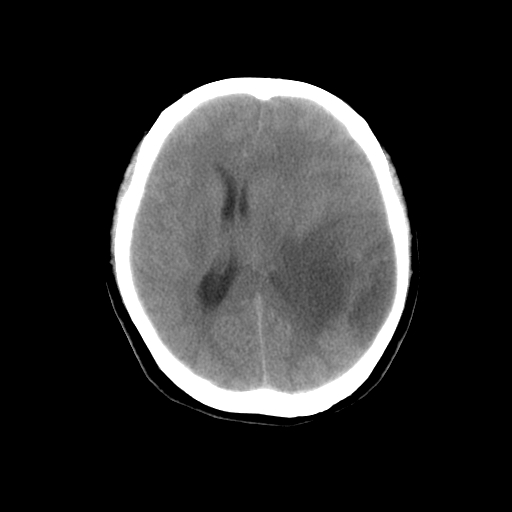

标题: CT14513:女性41岁,头部不适二月余,其它病史不详。请分析 [打印本页]

标题: CT14513:女性41岁,头部不适二月余,其它病史不详。请分析

1.考虑:左侧颞顶叶星形细胞瘤。2.大脑镰下疝。

胶质瘤可能性大支持2-3级星形细胞瘤

1)考虑左侧颞顶叶胶质瘤。2)左侧颞顶部慢性硬膜下血肿?3)大脑镰下疝。